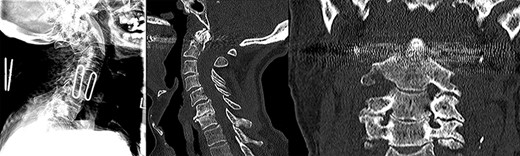

A 92-years-old man was immediately brought to the emergency department with complaints of neck pain following a fall down a flight of stairs at home. He had no comorbid illnesses and was neurologically intact. Imaging confirmed isolated type II odontoid fracture for which he had ACSF the following day. Postoperatively, he experienced dysphagia and further history revealed that he had repair of a zenker’s diverticulum ~40 years prior. A small lump was palpable in the left cervical region at the site of a previous surgical scar. Speech and language therapist, otorhinolaryngologist (ORL) and the geriatric teams were consulted while he was fed with liquid diet via a fine bore feeding tube. Preoperative cervical spine images (Fig. 1) as well as video fluoroscopy performed pre- and post-re-excision of recurrent zenker’s diverticulum (Fig. 2) are shown.

Preoperative lateral plain cervical radiograph (left), mid-sagittal (middle) and coronal (right) CT scans showing Grauer type IIB odontoid fracture without exaggeration of the atlantodental interval (ADI) suggestive of an intact transverse atantal ligament (TAL).